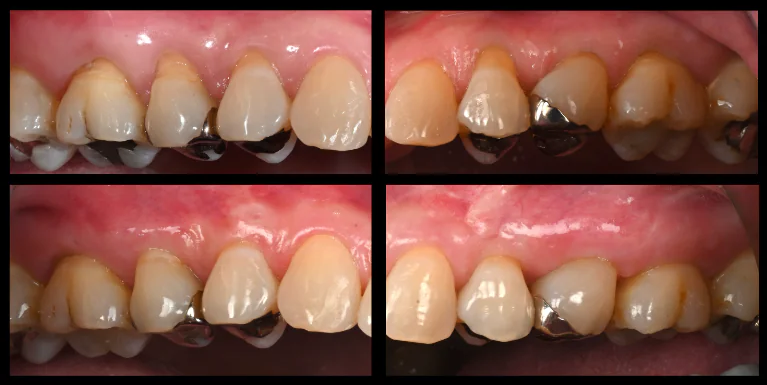

術前

術中

術後

根面被覆

| 治療名 | 前歯インプラント、根面被覆 |

|---|---|

| 治療説明 | 前歯4本の抜歯が必要となったためインプラントで回復することになりました。右上1,左上1に抜歯と同時にインプラントを埋入しました。右上2、左上2は結合組織移植を行いボリュームを回復することで、見た目と清掃性を向上させました。左右側方歯には根面被覆術を行って歯肉退縮を回復しました。 |

| 治療回数・期間 | 1年 |

| 副作用とリスク | インプラント治療は入れ歯やブリッジと比べて治療期間が長くかかることがあります。インプラント手術と結合組織移植は、違和感、痛み、腫れ、出血などが発生する場合があります。一時的なもので、2日〜1週間で治まります。 |

| 料金(税込) | 骨造成:110,000円(2本:220,000円) インプラント1次手術:220,000円(2本:440,000円) インプラント2次手術:55,000円(2本:110,000円) 結合組織移植:110,000円(4本:440,000円) 上部構造:220,000円(4本:880,000円) 根面被覆:396,000円 合計:2,456,000円 |